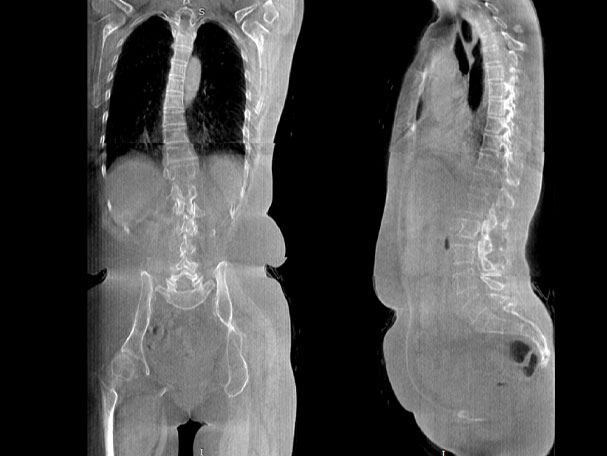

传统方法都是在二维平面,依靠棘突或椎弓根相对于椎体的偏移来评估脊柱侧凸。WR-3D可以更精准评估脊柱侧凸,制定手术方案,可以更直观地显示和量化椎体的平移和轴向旋转,术后评估更准确客观。

• 全身姿态评估

WR-3D能提供一种负重位状态下全身的姿态和三维空间任一平面平衡评估,使全脊柱术后评价更客观、真实 。通过各种临床参数包括骨盆、脊柱参数评价骨盆、脊柱平衡,避免由于髋膝屈曲造成的代偿性脊柱失衡的发生,WR-3D提供了三维空间任一平面平衡评估测量方法,可以更加定量地评估手术效果 。